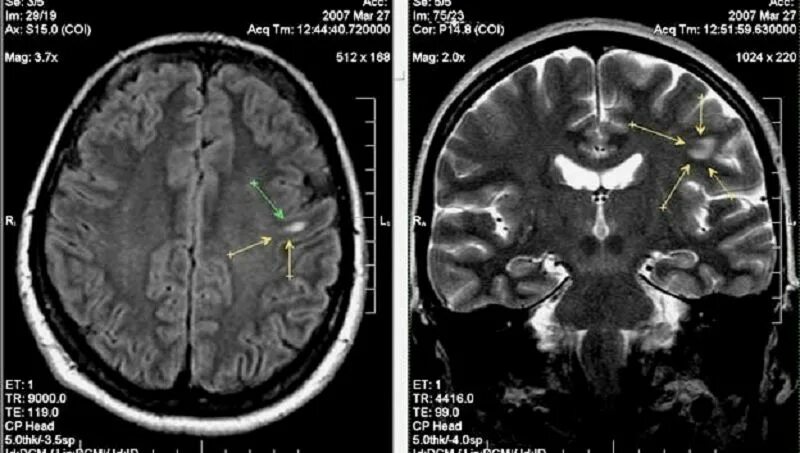

Вазогенные очаги белого